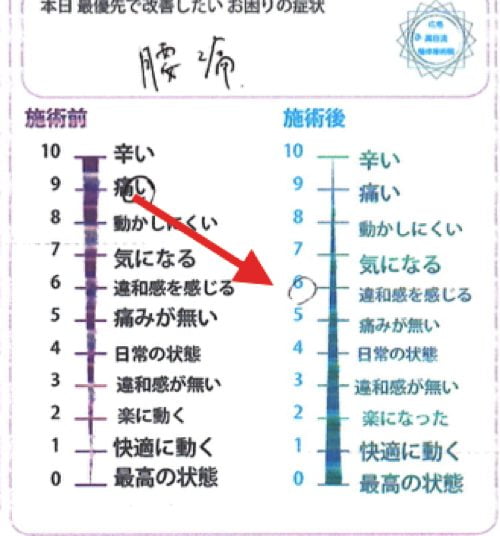

施術前後のアンケート